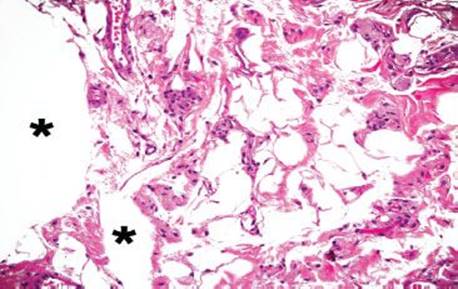

Figure 4.248 Air artifact. An alternative field shows large, bizarre air pockets (asterisks), which dissect the resident tissue. Lipomas do not tend to percolate around native structures such as ganglion cell clusters, nerves, fibrous tissue, and blood vessels, as seen in this example of an air artifact. Also, there is no epithelial lining and no nuclei to suggest a lymphovascular space or adipocytic lesion, respectively.

Figure 4.249 Air artifact. Air artifacts often inspire the most consideration around lymphoid aggregates in tissue submitted as a polyp: could the polyp represent a lymphoid aggregate with nearby air artifact or is the polyp a small lipoma?

Figure 4.250 Air artifact. On higher power, large, irregular air pockets seem to dissect the tissue (asterisks). Air artifacts are most problematic around lymphoid aggregates, where the air spaces can compress neighboring lymphoid cells and appear as if the air spaces have nuclei (arcs). In these scenarios, look carefully for definitive air pockets (asterisks). If definitive air pockets and adjoining lymphoid aggregates are seen, the indicated focus is most likely an air artifact. Deeper sections can be reassuring in ambiguous cases.